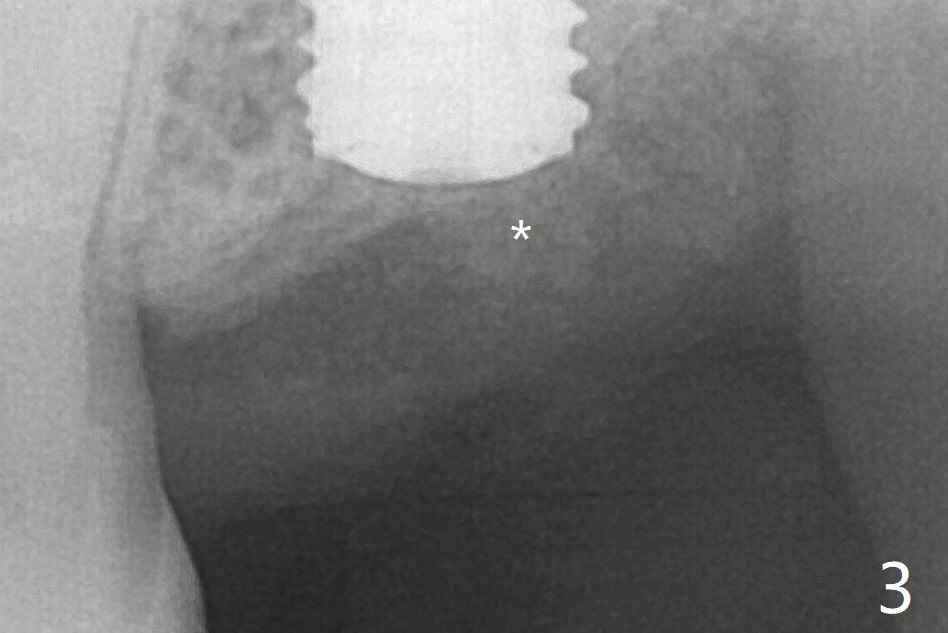

Following shorter drill sequence at #15, sinus round drills (18 and 19 mm long) are used to perforate the sinus floor without membrane tear. With autogenous bone for sinus lift (Fig.1 S), a 5x7.3 mm implant is placed with high torque in spite of using 5 mm cortical drill with 3 O-rings. Clinically there appears no hard tissue distal, although the bone density (graft bone in the 3rd molar socket) is low shown in bitewing (Fig.2 ^). Allograft is applied around the distal coronal portion of the implant before placement of Osteogen Plug and 4-0 PGA suture (Fig.3 *). Profile drill is required during uncover. With sensor I, there is less distortion and angulation (Fig.4, as compared to Fig.1 (sensor II)). A 5.5 mm profile drill is used prior to healing abutment placement.